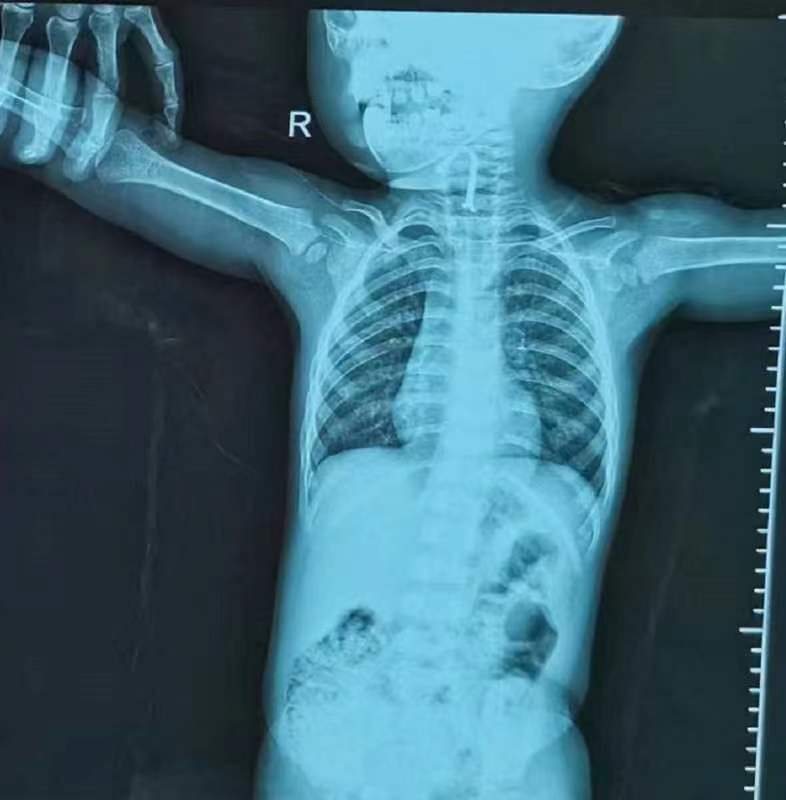

惊慌失措的家长赶忙将孩子送到武汉儿童医院,拍片发现有个不明金属物体卡在气管中间,当晚,耳鼻咽喉科医生急诊手术,用气管镜取出一个长约2厘米,宽7毫米LED发光二极管。